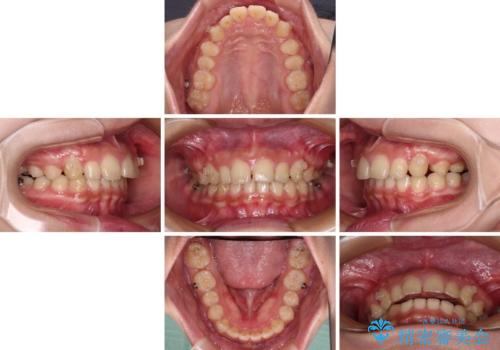

正面や横からの写真ではきれいに治っており、患者様は大変満足のいく仕上がりとなりましたが、深い咬み合わせの改善は不十分で、奥歯の咬み合わせも改善させることができませんでした。

インビザラインは、咬合力の強い方ですと、奥歯が歯肉内にめり込んでしまうため、前歯が強く接触してしまうことがあります。

こちらの方は、奥歯はしっかりと噛んだのですが、歯肉にめり込んでしまったことで、歯肉が腫れやすくなってしまいました。